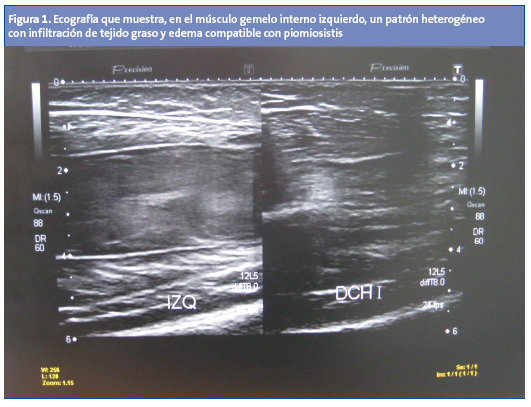

Se trata con amoxicilina/clavulánico intravenoso (IV), pero al cuarto día presenta un empeoramiento de la tumefacción. Se le realiza una radiografía del miembro inferior que muestra un aumento de partes blandas, y una ecografía que muestra un músculo gemelo interno con hipoecogenicidad y tumefacción con pérdida de patrón fibroadiposo, que refleja edema e infiltración de tejido graso compatible con piomiositis. No hay constancia de absceso susceptible de drenaje (Fig. 1).